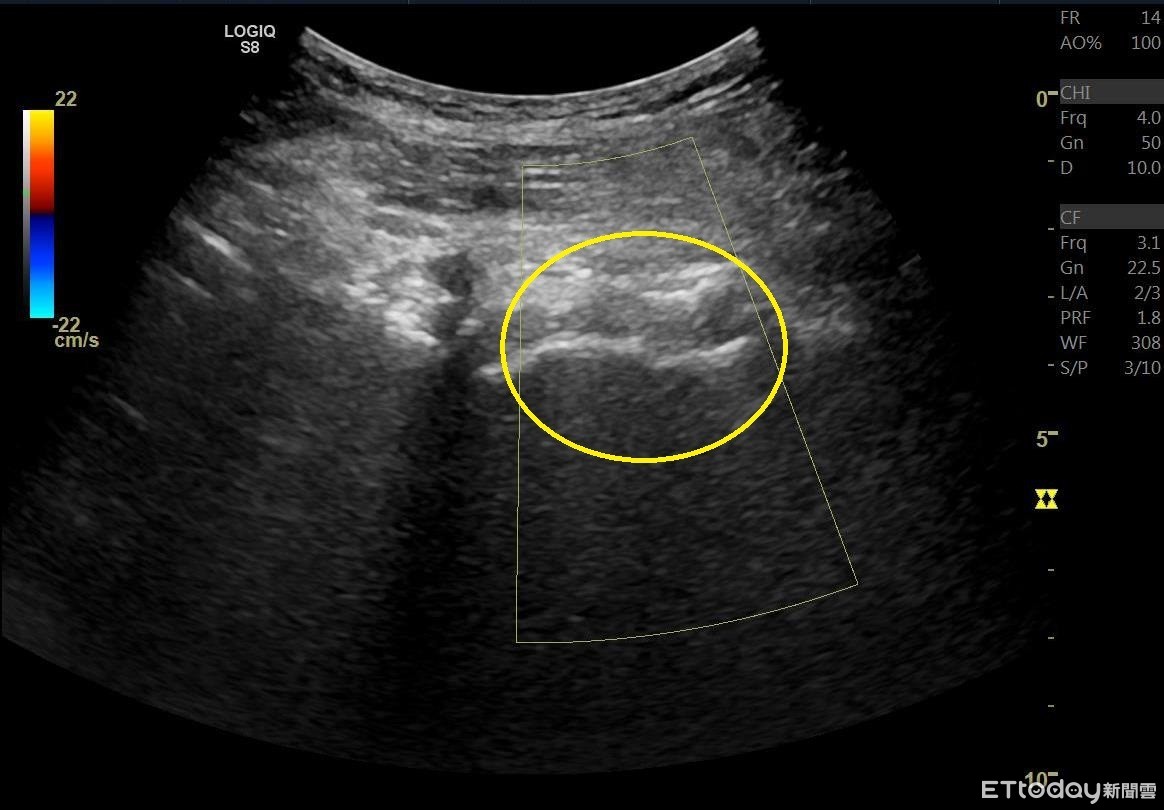

▲南投醫院以超音波導引注射,有效緩解年長患者的退化性髖關節疼痛。(圖/衛福部南投醫院提供)

南投周姓獨居老婦平日喜歡在中興新村散步賞荷,近年來漸覺右邊髖關節「卡卡」的、且僵硬疼痛,常走數百公尺就無法繼續;就醫後診斷為髖部退化性關節炎,因擔心開刀會有術後照顧和影響未來生活的問題,經衛福部南投醫院施行「關節內髖關節超音波導引注射治療」後,周婦髖關節疼痛大幅改善,現能連續散步4公里。

周建文指出,患者可依嚴重程度接受藥物、復健治療,若症狀未改善則可能需手術治療,而現在可由醫師評估,考慮關節內髖關節注射治療;因髖關節位於身體深處無法觸及,加上股神經、動脈和靜脈非常靠近前髖關節,導致執行診斷注射時所需的準確性和挑戰性更高,通常建議使用影像引導注射。

周建文說,大多數臨床醫生會在透視X光檢查下進行這些注射,但有費用昂貴且有輻射暴露的缺點,而超音波導引注射與透視X光和電腦斷層(CT)相比,並沒有絕對的禁忌症,不產生輻射、不需注入顯影劑和麻醉,也不需住院,於門診即可施行,目前已廣泛應用於疼痛醫學和運動醫學,讓疼痛患者有多一種治療選擇。